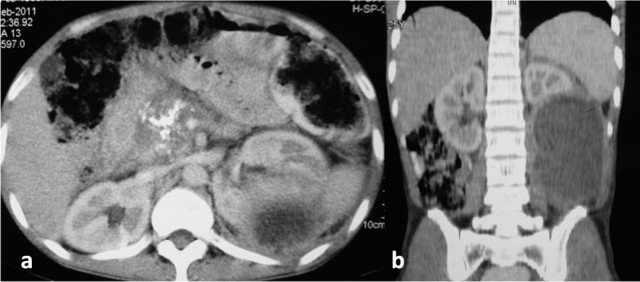

On evaluation, he was febrile (39°C) and had an 8x8 cm tender ballotable lump in the upper left abdomen. Ultrasonography of the abdomen showed a 12x8 cm left perinephric collection, and a percutaneous pig-tail catheter drain was placed under ultrasound guidance. It drained 600 mL of purulent fluid for the first two days and, thereafter, about 100 mL of hazy fluid per day. A bacterial culture of the fluid isolated alpha hemolytic Streptococci sensitive to ampicillin and aminoglycosides, and he was started on parenteral amikacin. The pig-tail catheter drain continued to drain about 100 mL fluid per day for more than 7 days although his fever subsided. A routine urine examination and a bacterial urine culture did not reveal any evidence of infection. Blood sugar was normal and HIV serology was negative. Electrocardiography and echocardiography were also normal. In view of the persistent drain output, the fluid was further investigated; the amylase level in the fluid was found to be 2,566 U/L (reference range: 20-96 U/L) and the corresponding serum amylase was 76 U/L. Contrast-enhanced computerized tomography (CECT) of the abdomen was carried out which showed dense foci of calcification in the head of the pancreas, a mildly prominent pancreatic duct with a 12.3x8.6 cm hypodense collection in the posteroinferior part of the left kidney, displacing it anteriorly and eroding its posteroinferior capsule (Figure 1). There was no evidence of fluid collection anywhere else in the abdomen. A diagnosis of chronic calcific pancreatitis with a left perinephric abscess was made and a gastroenterological opinion was sought. His serum parathyroid hormone and triglyceride levels were normal. There were no signs of pancreatic exocrine or endocrine insufficiency. He underwent endoscopic retrograde cholangiopancreatography (ERCP) but selective pancreatic ductal cannulation could not be achieved, possibly because of the dense calcification. A needle knife sphincterotomy of the ampulla of Vater was carried out in the direction of the 1 o’clock position, from the ampullary orifice. The patient had a reduction in drain output following this procedure. On the 11th day, the drainage stopped completely; repeat ultrasonography showed no residual collection and the pig-tail catheter drain was removed. He was asymptomatic on discharge and a follow-up CECT scan one month later showed complete resolution of the perinephric abscess (Figure 2).

Figure 1. a. CECT abdomen showing calcification in the head of the pancreas and the left perinephric abscess. b. Coronal section showing the left perinephric abscess. |